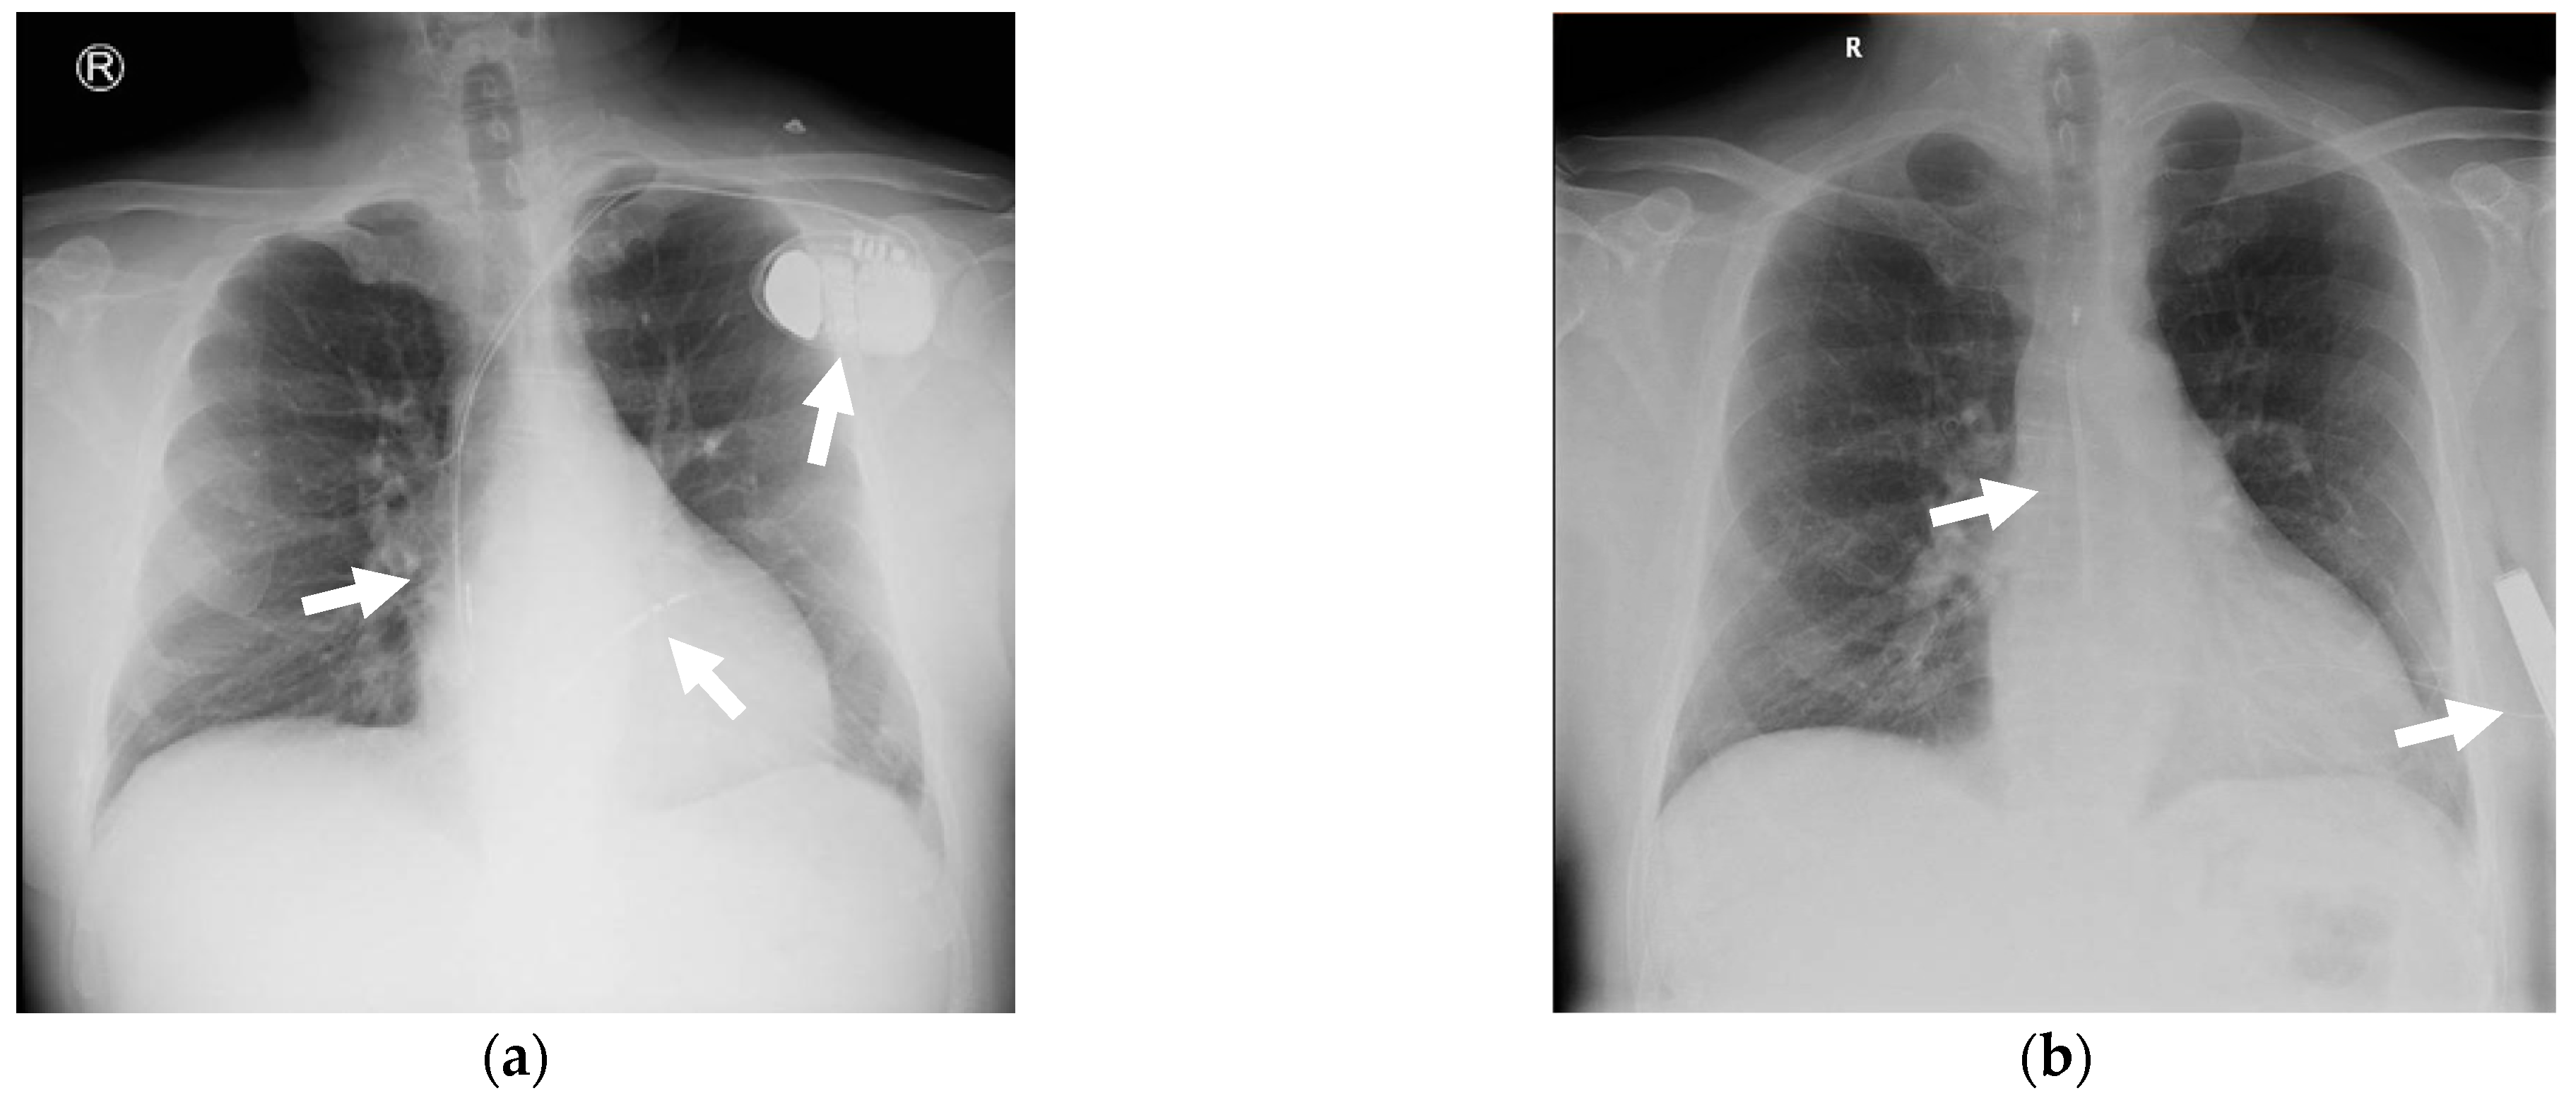

2. Case Presentation